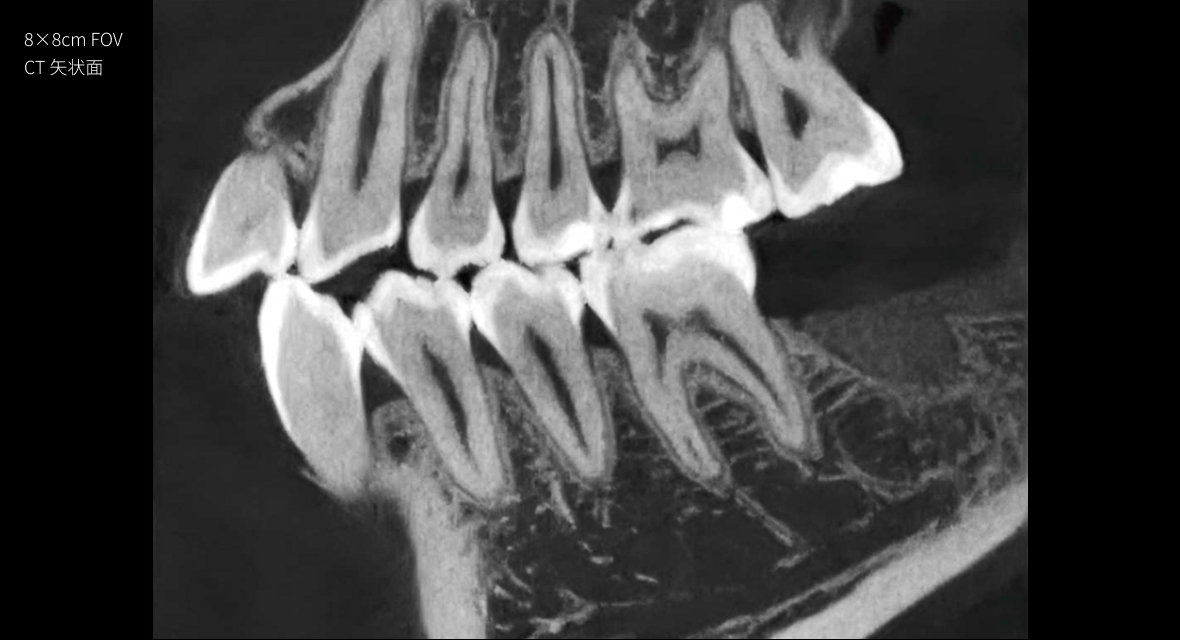

只需一次单圈扫描即可获得CT、3D全景和3D正/侧位影像,并能同时生成3D TMJ视图

提高诊疗效率,避免过度检查,减少患者所受的辐射

• CT

CT